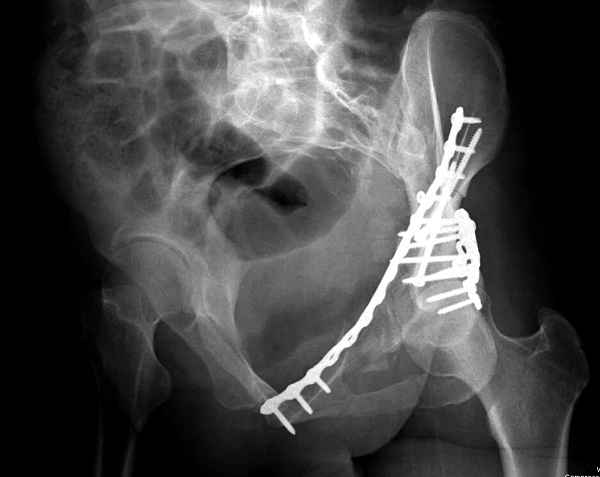

Из того минимума, что представлено, мне кажется, мы имеем дело с двухколонным переломом вертлужной впадины. Обычно медиальный (центральный) "вывих" головки встречаются в сложных двухколонных переломах со смещением.

По-моему, надо готовить больного к будущей артропластике, но без опоры на задний столб невозможно удержать протез. Опорная конструкция (кольца и т.д.) должны иметь опору, и поэтому мы бы сделали реостеосинтез задним доступом. При надобности остеотомия и рутинная фиксация с межколонными винтами.

Здесь несколько вариантов двухколонных свежих переломов, которые были оперированы из одного-заднего, а также из двух: переднего и заднего доступов.